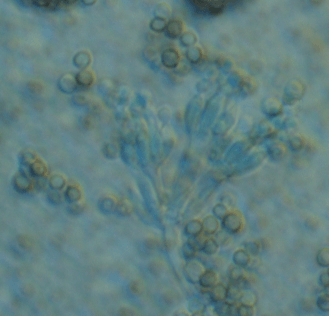

1928년 알렉산더 플레밍은 실험 중 우연히 세균 배양 접시에 곰팡이가 떨어져 있는 것을 관찰하게 됩니다. 그는 곰팡이가 세균의 생장을 억제하고 있다는 점에 주목하였으며, 이로부터 페니실린이 분리되었습니다. 이때 관찰된 진균이 Penicillium notatum이었습니다. P. notatum은 일반적으로 토양, 공기 중에서 흔히 발견되는 사상균으로, 자연상태에서도 항균 물질을 생성하는 능력을 가지고 있습니다. 플레밍의 발견은 우연이었지만, 진균학적으로 매우 중요한 의의를 지닙니다. 당시로서는 처음으로 진균이 인류 건강에 결정적 영향을 끼친 사례였으며, 이후 미생물학과 약학의 패러다임을 전환시킨 계기가 되었습니다.

처음 발견된 P. notatum은 이후 연구가 진행되면서 여러 유전적, 생리학적 분석을 통해 재분류되기 시작합니다. 미국에서는 페니실린 대량 생산을 위해 다양한 곰팡이 균주를 수집하고 스크리닝했으며, 가장 효율적으로 항생제를 생성하는 균주는 Penicillium chrysogenum으로 불리게 됩니다. 그런데 분자생물학 기술이 발달함에 따라 과거의 P. chrysogenum 균주들이 실제로는 P. rubens라는 종에 더 가깝다는 사실이 밝혀졌습니다. 따라서 현재는 산업용으로 쓰이는 균주의 정확한 명칭이 Penicillium rubens로 통일되고 있습니다. P. rubens는 P. notatum보다 페니실린 생성 효율이 높고, 유전적 조작에도 유리하다는 특징을 지니고 있습니다. 진균학에서는 이처럼 분류학적 재정의가 항생제 생산의 정확성과 효율성에 직접적인 영향을 미친다고 보고 있습니다.

진균이 항생제를 생성하는 생물학적 배경은 경쟁 억제 전략에서 기인합니다. Penicillium 속 진균은 자신 주변의 박테리아를 억제하기 위해 항균 물질을 분비하며, 이는 곧 사람에게 유용한 항생제가 됩니다. 페니실린은 세균의 세포벽 합성을 방해하여 세포 분열을 막는 작용을 하며, 진균의 대사경로에서 자연스럽게 생성되는 2차 대사산물입니다. 특히 진균학에서는 페니실린 생합성 경로에 관여하는 유전자 클러스터를 분석하여, 유전자 조작을 통해 생산 효율을 높이는 방법을 연구합니다. 이러한 유전자들은 환경 조건, 배양 온도, 배지 조성에 따라 발현 수준이 달라지기 때문에 발효 조건 최적화도 중요한 연구 과제입니다.